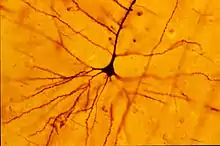

About a decade after Broca's area was recognized as a movement control area of the brain, Vladimir Betz used a new technique, the Golgi stain, to identify a type of giant pyramidal shaped cells that are movement control cells of the brain. These "Betz cells" are among the largest neurons of the human brain and they are depleted from the brains of patients with Lou Gehrig's disease.